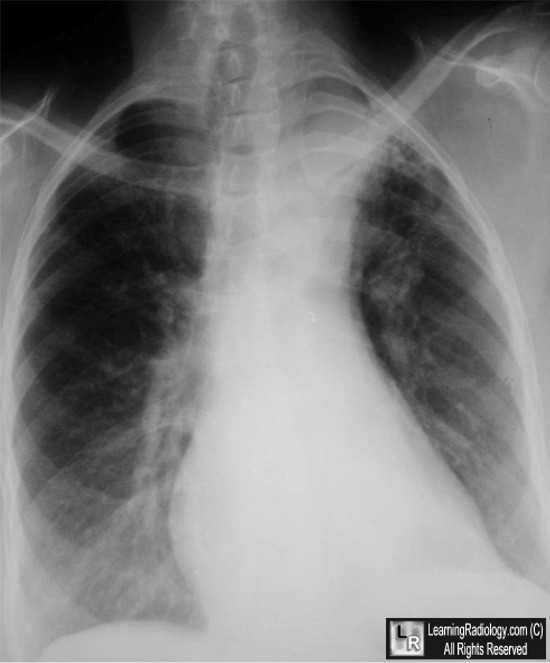

Cervical Aortic Arch. Above: Axial, contrast-enhanced CT scan of the upper thorax shows the aortic arch (black arrow) extending above the level of the clavicles. Below: Frontal radiograph of the chest demonstrates the cervical arch at the apex of the left lung (white arrow) above the clavicles. There is no aortic arch in the normal location. The aorta descends on the left.

For this same photo without the arrows, click here and here